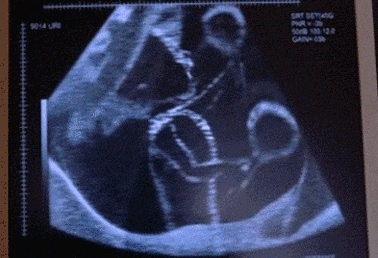

在正常情况下孕妇会在孕18-20周感受到胎动,刚开始还是比较轻微的胎动,而随着时间的推移,胎动会越来越明显,几乎在每天的同一时间点,准妈妈都能明显的感觉到胎动的发生,这个时候相信很多准妈妈都会好奇宝宝在肚子里为什么会动、都是怎么动的,现在就让小检陪你一起了解一下吧 胎儿蠕动的时候是在干嘛? 一.妈妈肚子波浪式蠕动 孕妈妈有时候会发现自己的肚子呈现波浪式的蠕动,这时候就意味着宝宝吃饱喝足,心情愉快,妈妈们可以适当和宝宝说会儿话,宝宝在心情舒畅的情况下,是很愿意倾听妈妈的心声的,虽然他们可能听不懂,但也会增加妈妈和宝宝的熟悉感哦。 二.妈妈肚子鼓起来 妈妈的肚子鼓起来,可能是因为宝宝睡醒了在伸懒腰呢。甚至有些妈妈的肚子鼓出一个手掌的形状或者屁股的形状,这时候妈妈就能看清楚宝宝的手掌和屁股了。遇见这种情况的时候,不妨赶紧拿相机记录下来,毕竟这样的场景是十分难遇到的哦。 三.妈妈的肚子被踢 妈妈的肚子被突然踢一下或者是突然鼓起来,这时候宝宝可能是受到了某种惊吓。比如妈妈关门时声音过大,妈妈所处的环境噪音很大,或者妈妈一些动作太快,都会让宝宝惊吓到。妈妈的肚子被踢,说明宝宝有脾气了,这时候妈妈可以轻轻摸肚子安抚宝宝,让宝宝慢慢平静下来。 四.妈妈的肚子有节奏地动 妈妈肚子偶尔会有这种情况:节奏明显地动,这时候就意味着宝宝在打嗝。宝宝打嗝一般会持续五六分钟,在宝宝打嗝的过程中,妈妈可以轻轻抚摸宝宝,不用过于担心宝宝是否会因为打嗝难受,几分钟之后宝宝自己就会停止打嗝。宝宝打嗝还能提前锻炼心肺功能,而且在宝宝打嗝的时候,妈妈还能判断出来宝宝的头在哪里哦。 宝宝在妈妈肚子里翻身、打嗝、受惊吓、发脾气,都是宝宝有生命力的表现,孕妈妈应该为此感到高兴,宝宝的生命力这么顽强,生出来一定健健康康的。 但胎动不是越厉害越好,如果胎儿一直都是特别好动,这属于良性胎动;但如果突然动的特别频繁,孕妈咪就要注意了,这可能是个警讯,例如受外力撞击,或胎盘剥离,这时候胎儿会有暂时性激烈的活动,没多久便安静下来,胎动很明显减少,甚至没有胎动,这种情形应该立即就医! 在正常情况,胎动1小时不少于3~5次,12小时明显胎动次数为30~40次以上。有的胎儿12小时可动100次左右,只要胎动有规律,有节奏,变化不大,即证明胎儿发育是正常的。 如何判断异常胎动? 到了怀孕后期,胎动会逐渐减少,这是正常现象。但是如果12小时胎动少于20次,则为异常;少于10次,则表明胎儿有危险,在子宫内有缺氧现象;胎动次数明显减少直至停止,是胎儿在宫内重度窒息的信号。在妊娠28周后,胎动部位多在中上腹,很少出现小腹下部。如果小腹下部经常出现胎动,则可视为异常,表明胎位不正常,多为臀位或横位,容易造成分娩困难,应及时就诊。 所以,在享受宝宝运动的同时,还要注意定期孕检,严密观察胎儿的发育情况哦~ 觉得有用的小伙伴可以点个赞,加个收藏哦~ 关注家家检检,了解更多孕期知识,好孕更轻松!